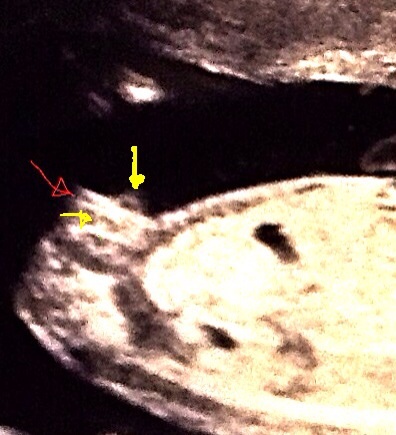

So went for my gender scan and baby didn't want toco operate and just wanted to keep rolling up in a ball with its head a s far down as you can possibly get, I've now been rebooked, anyway we were so luck to get a side shot of bubba and I can still see a clear girl nub that hasn't shrunk since my 13 week scan! Is this a really protruding clitoris? Slightly worried!!